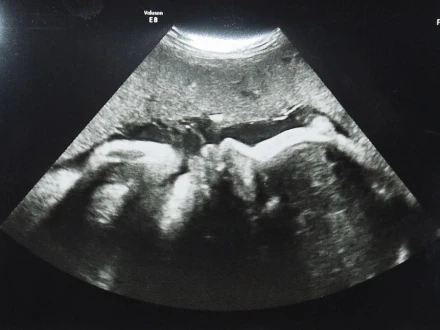

Ezen a héten volt a harmadik, egyben utolsó ultrahang. Erre azért volt szükség, hogy ellenőrizzék, elég nagy-e a baba, mivel az én testtömeg-indexem alacsony. Szerencsére minden rendben volt.